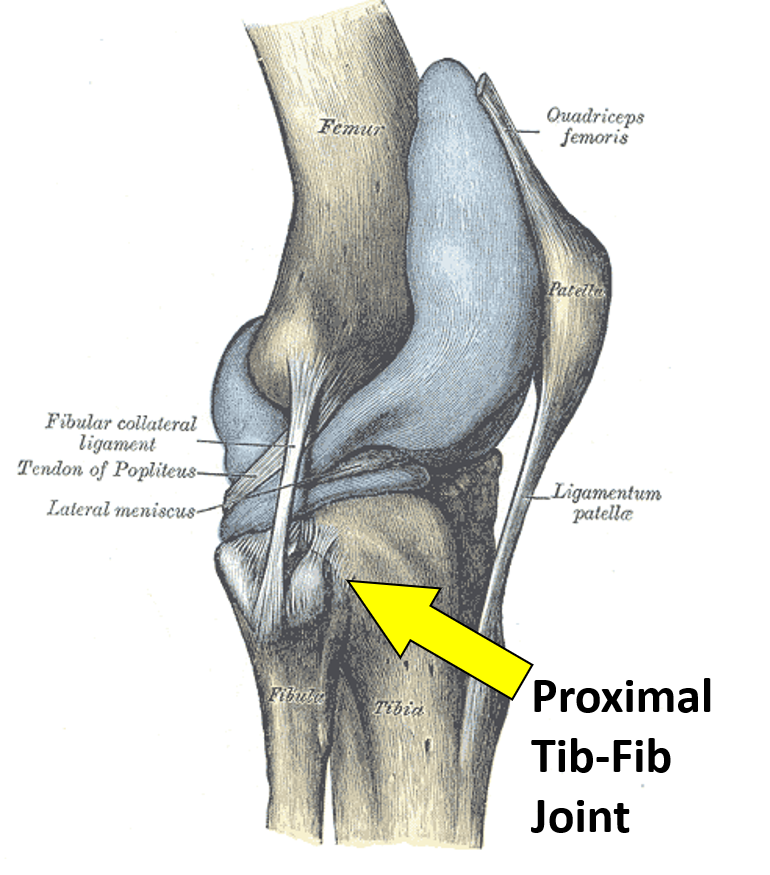

Tibiofibular Joints – Proximal – Distal – Interosseous Membrane …

Fibular Head Pain? Here’s What To Do – Centeno-Schultz Clinic

Fibular Head Pain? Here’s What To Do – Centeno-Schultz Clinic

Fibular Head Pain? Here’s What To Do – Centeno-Schultz Clinic